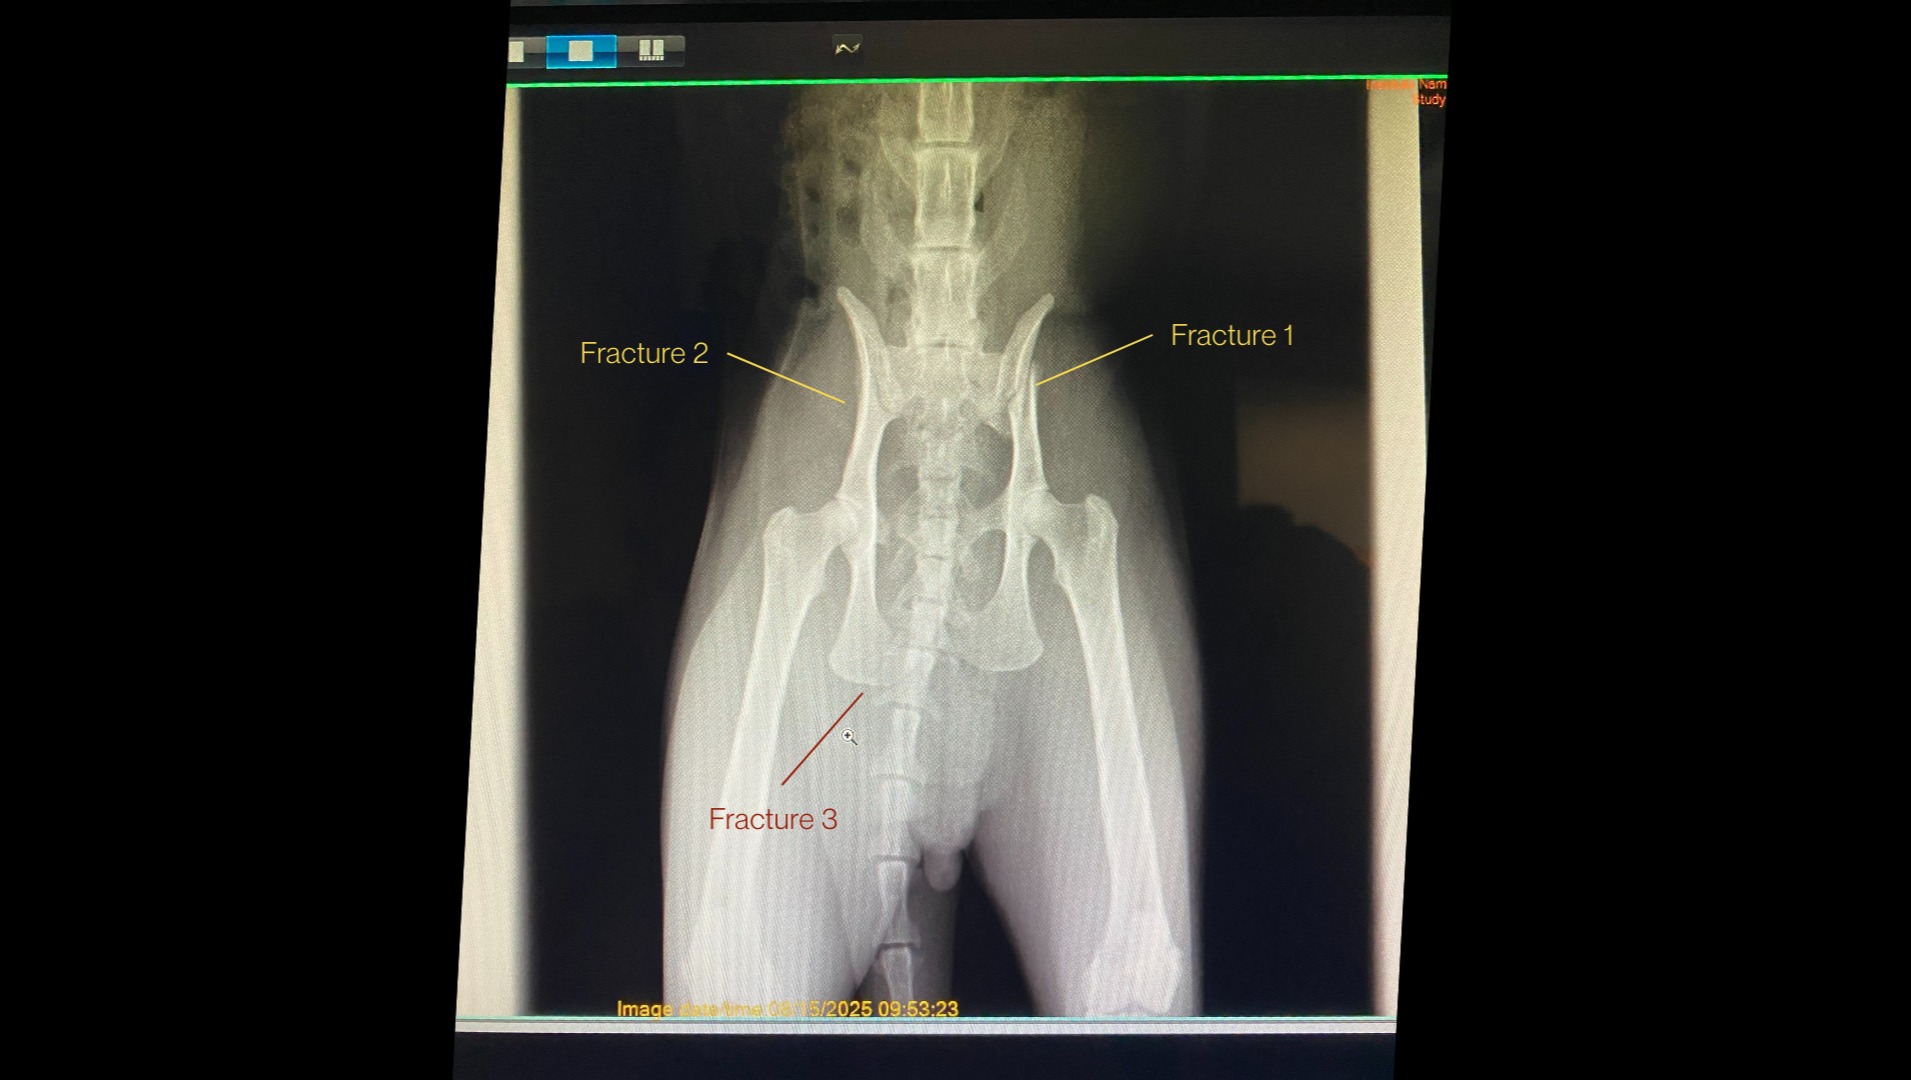

I am really sad to share that this past week Mikko was in a big accident. I am not fully sure what happened but the impact of his wounds indicate that he was likely hit by a car. My poor boy has a broken pelvis and is experiencing a lot of pain.

I have taken him to two vets to see how he can be helped. The first vet was not hopeful about a recovery and expressed that euthanasia was the only option. Mikko still is able to move his back legs and has feeling in his legs and paws as well. This option didn't feel right to move ahead with and so I sought out a second opinion. This second vet has taken x-rays and bloodwork to determine Mikko's injuries. She said that cat's are very good at healing and it is very possible that Mikko's major pelvis injury could be healed, although there are some complications and he will require lots of medical attention. If I want to continue treating Mikko's injuries and hope for his recovery, I need financial support to pay for his veterinary bills.